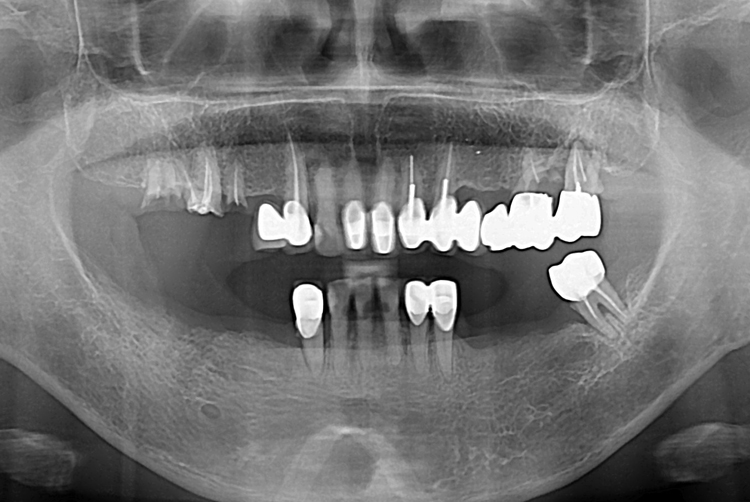

[임플란트] 어금니 임플란트

치료전 : 2017-09-01